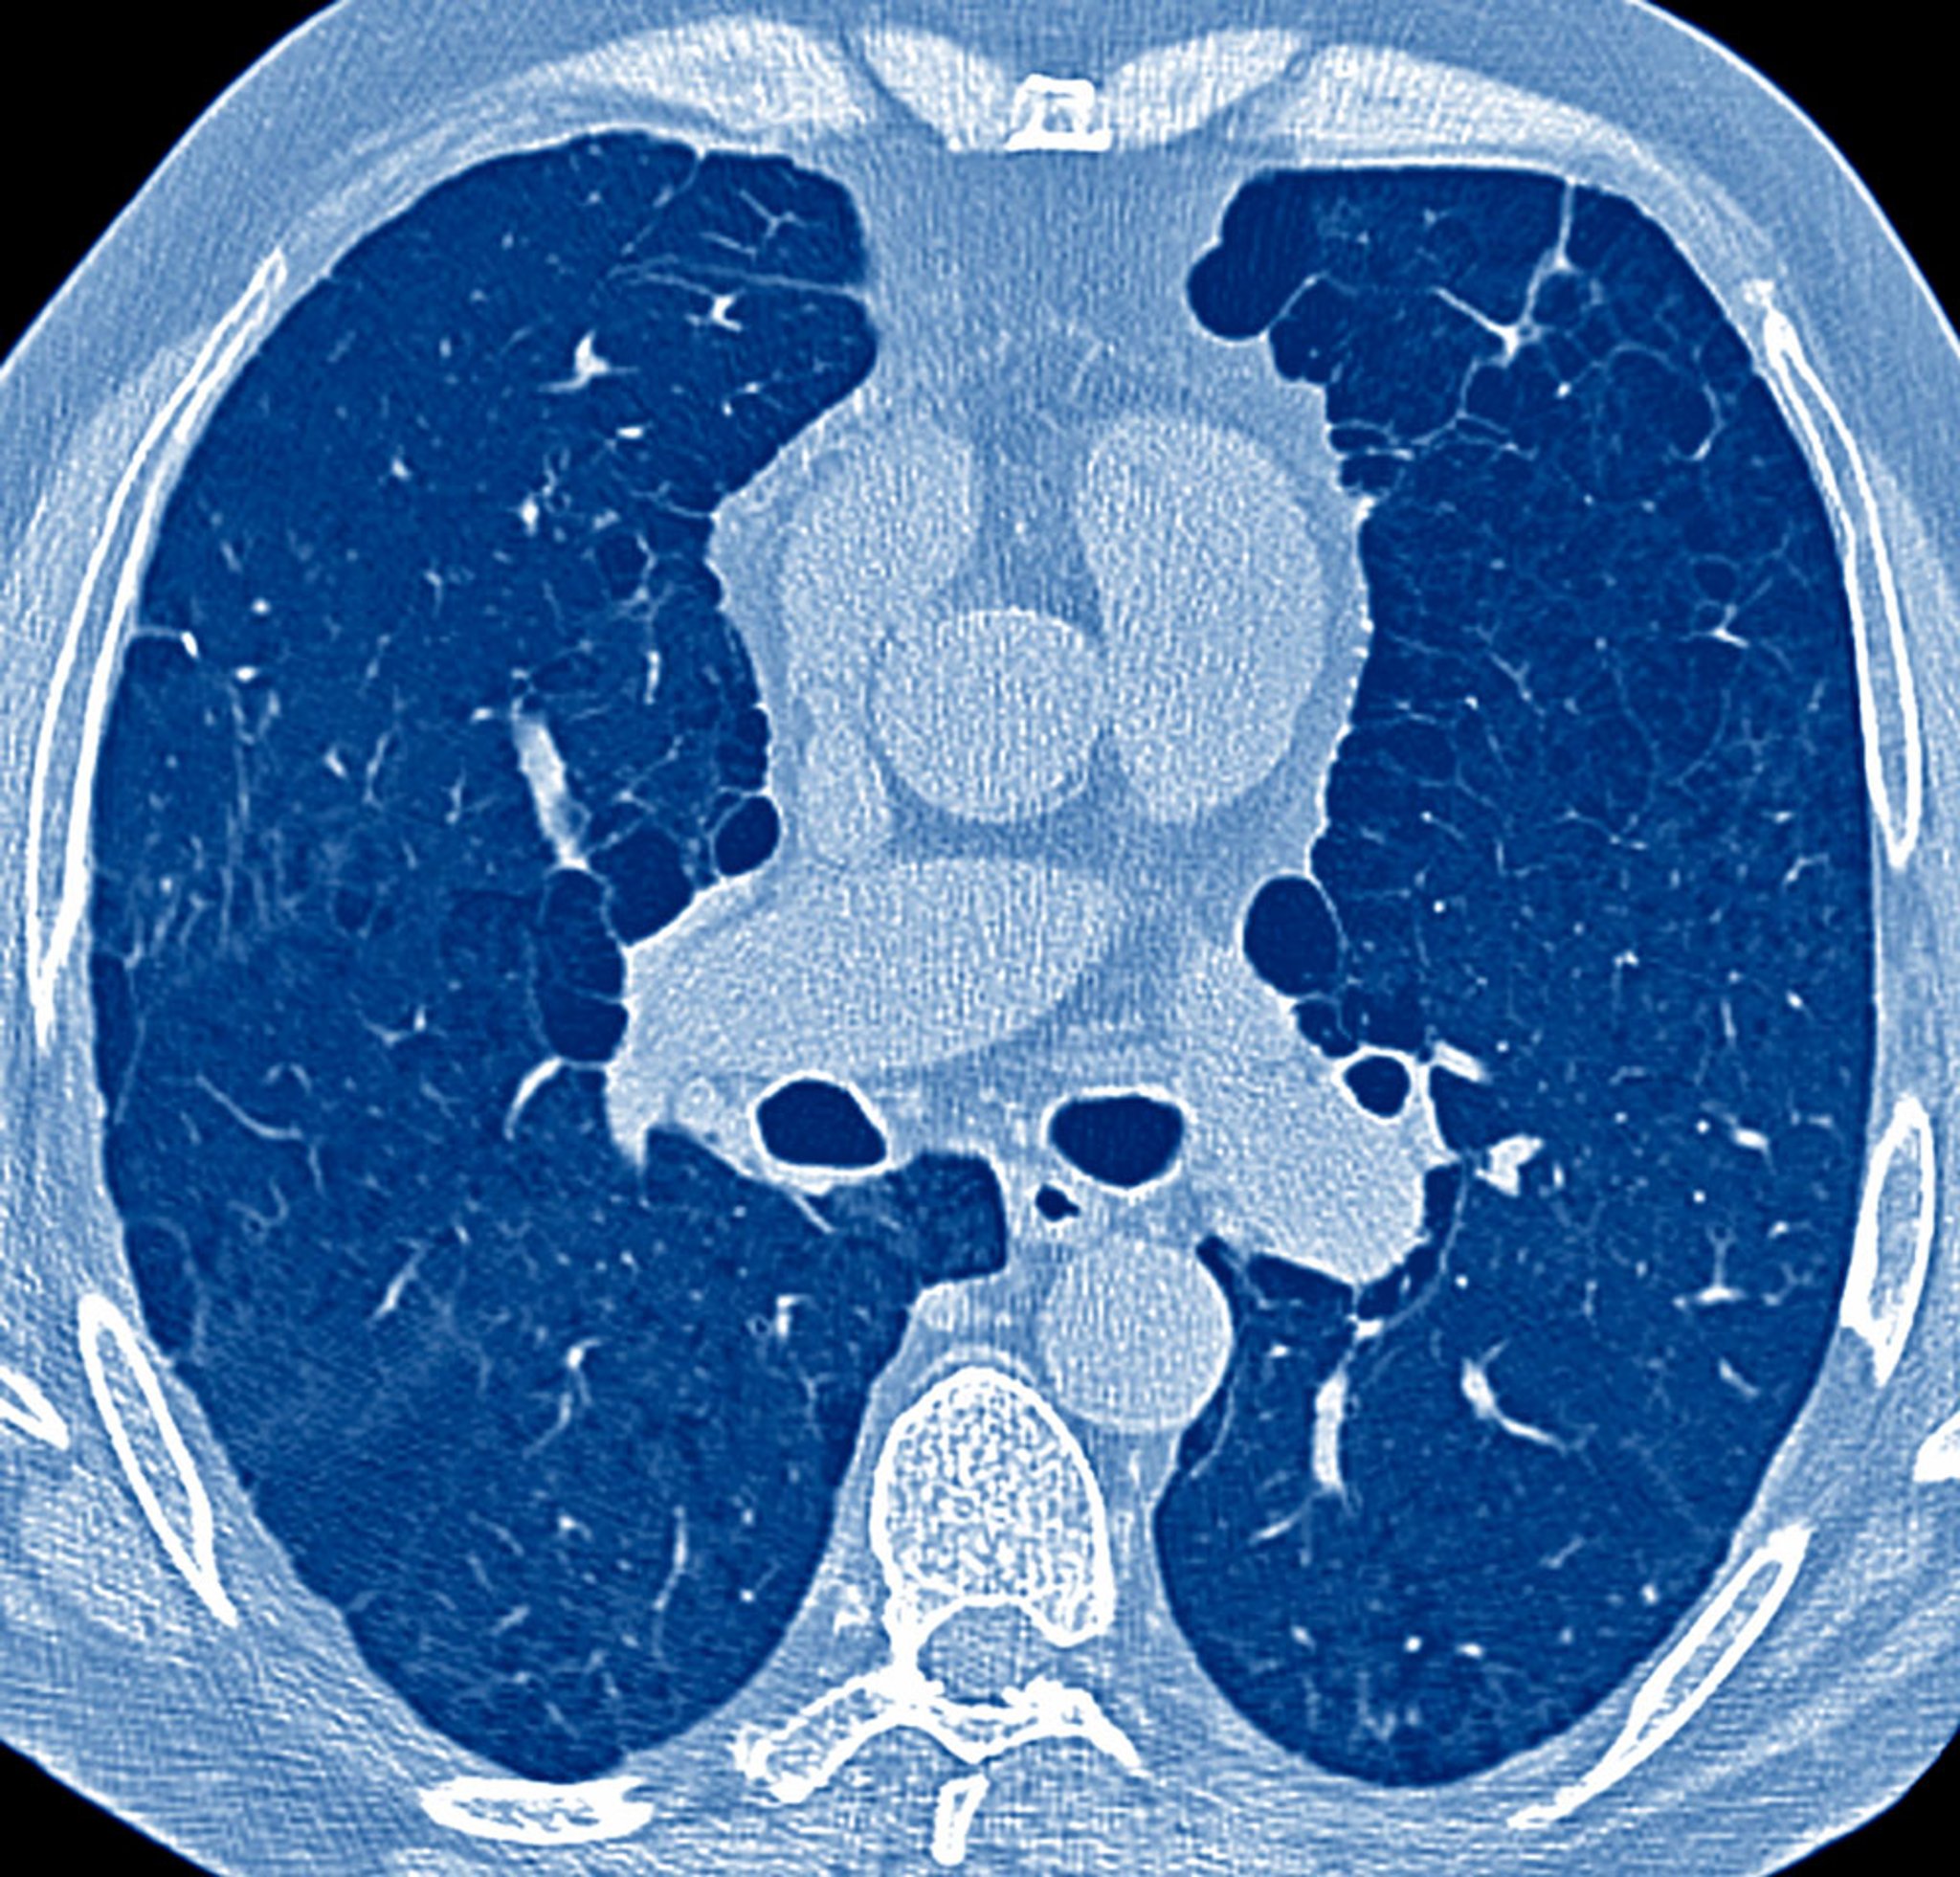

Các thành phần chính trong việc đánh giá bệnh nhân có các triệu chứng về phổi là tiền sử, khám thực thể và trong nhiều trường hợp là phim chụp X-quang ngực. Các phần này thiết lập việc cần thiết phải làm các xét nghiệm tiếp theo, có thể bao gồm kiểm tra chức năng phổi, phân tích khí máu động mạch (ABG),chụp CT ngựccác kiểm tra chẩn đoán hình ảnh ngực khác, siêu âm tim, thử nghiệm đi bộ 6 phút, nghiệm pháp gắng sức tim phổi, thông tim phải, nội soi phế quản và sinh thiết phổi.